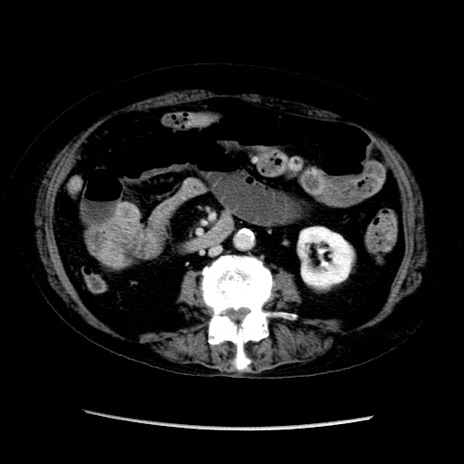

症例14(横断像)

【症例】 90歳代女性

【主訴】 腹痛・嘔吐

【現病歴】今朝から左側腹部痛を認めた。 経過観察していたが、嘔吐を認めたため来院。

【既往歴】 子宮癌術後

【身体所見】 意識清明、BP 127/54mmHg、P 98bpm Sp02 95%(RA)、BT 35.8°C、腹部平坦・軟腸ぜん動音聴取良好、右下腹部圧痛(+) 反跳痛なし

【データ】WBC 9800、CRP 0.46